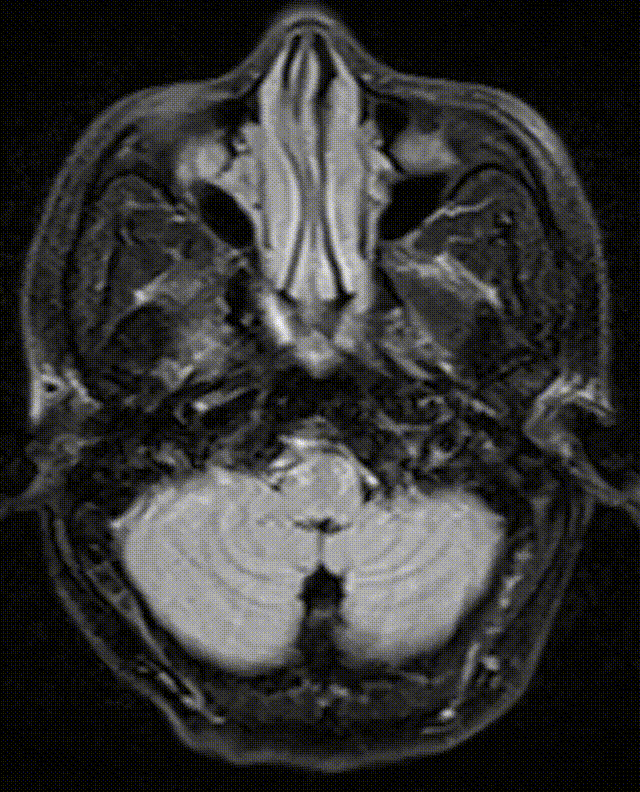

➢急诊头颅CT

-

脑动脉硬化;

鼻窦炎。

术后第二天复查CT:脑干、双侧小脑半球、枕叶、丘脑脑梗死。

急诊颅脑CT平扫未见异常,必要时MRI检查。

术后复查CT:双侧大脑及小脑半球稍肿胀。

术后MRI:脑干新发梗死。